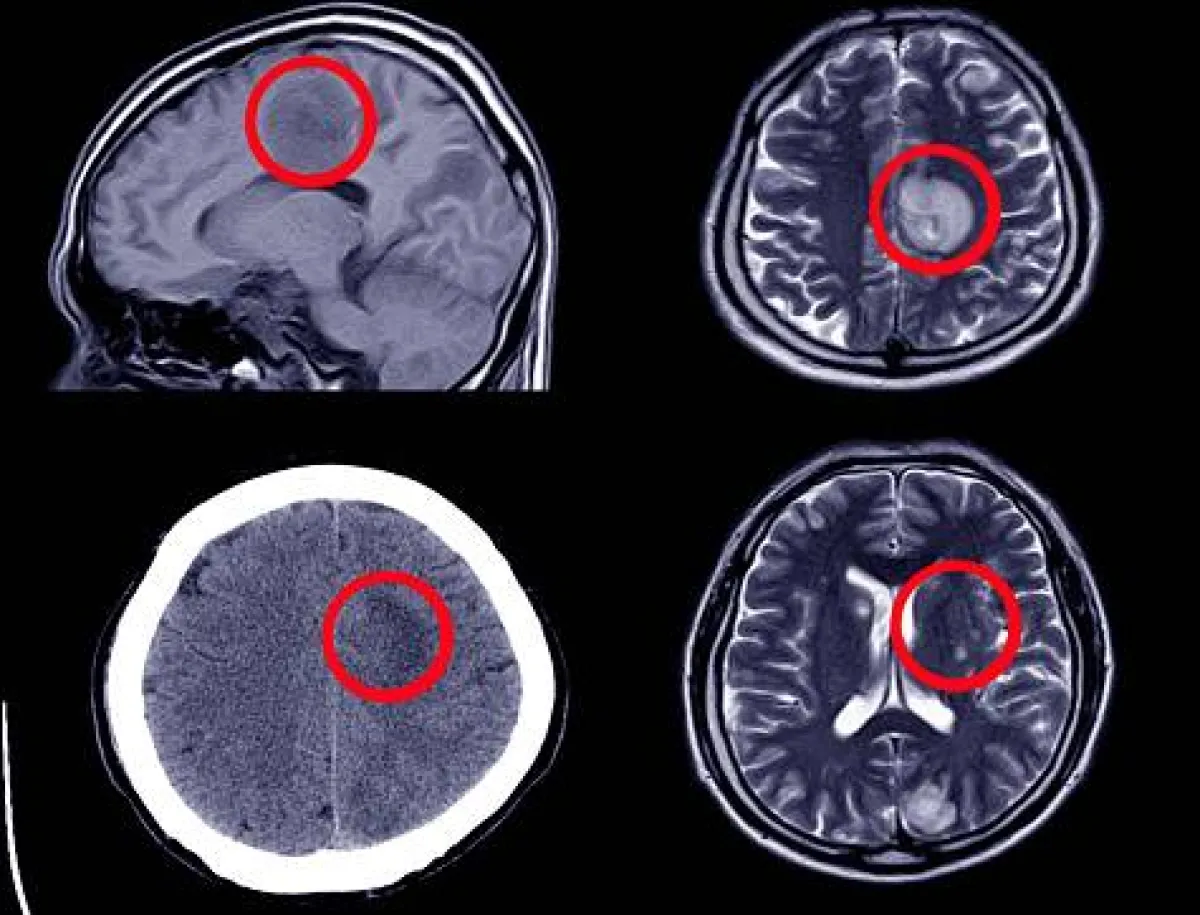

فقط عندما تم نقل "كرال" إلى غرفة الطوارئ في مستشفى سيدارز-ديناي مارينا ديل ري، كشف التصوير المقطعي أنها مصابة باستسقاء الرأس، والذي يحدث عندما يتجمع الكثير من السوائل حول الدماغ، مما يؤدي إلى ضغطه وإحداث مشاكل في التوازن والمزاج. يتم تشخيصه في حوالي اثنين من كل 1000 أمريكي بعد الولادة. بعد التشخيص، خضعت "كلوي" لعملية جراحية لإزالة السوائل الزائدة، وخرجت من المستشفى بعد خمسة أيام، وبدأت تتعافى ببطء. بعد العملية الجراحية، تحسنت حالة "كلوي" لدرجة أنها الآن تعيش حياتها بشكل طبيعي دون أي مشاكل كبيرة، حيث استعادت قدرتها على قيادة السيارة، وتحتفظ بوظيفة، وانضمت إلى كلية التصميم مرة أخرى في سان فرانسيسكو. قالت والدتها "أليسون": "لو لم يجرِ الأطباء هذا الفحص، لكانت "كلوي" قد ذهبت إلى مرفق الطب النفسي هذا، وستستمر في العلاج كمريضة نفسية". في حين قالت "كرال": "بالنسبة لي، فإن تشخيصهم لي يعني فرصة الحصول على الحياة التي لطالما أردتها، وأنني اعتقدت أنني لن أتمكن من الحصول عليها".

استسقاء الرأس -المعروف أيضاً باسم الماء على الدماغ- هو حالة نادرة يمكن أن تكون موجودة عند ولادة شخص ما أو تتطور خلال حياته. يحدث ذلك عندما يتم انسداد قنوات تصريف السائل الدماغي الشوكي -الذي يحيط بالدماغ ويعمل على تبطينه- مما يؤدي إلى تراكم السائل. في المقابل، يمكن أن يبدأ هذا في ضغط مناطق الدماغ، مما يؤدي إلى ظهور أعراض تشمل تقلب المزاج والصداع والغثيان والقيء. ويشمل العلاج قطع ثقب في الجمجمة واستخدام أداة بحجم قلم لإزالة الانسداد وإعادة فتح القنوات، مما يضمن تصريفاً طبيعياً. عندما تُترك دون علاج، يمكن أن تؤدي الحالة إلى تلف دائم في الدماغ. في حالة "كلوي"، كان تراكم السوائل حول دماغها يضغط على فصوصها الأمامية على الجزء الخلفي من جبهتها. وتشارك هذه المنطقة في الذاكرة، واتخاذ القرار والسيطرة على العواطف. قال الأطباء إن من المحتمل أنها كانت تعاني من الحالة منذ الولادة، وأن دماغها كان يعوضها لأطول فترة ممكنة. وكشفت مستشفى سيدارز-ديناي مارينا ديل ري في كاليفورنيا عن القصة كتحذير للعائلات الأخرى التي تكافح من أجل تشخيص حالة أطفالها.